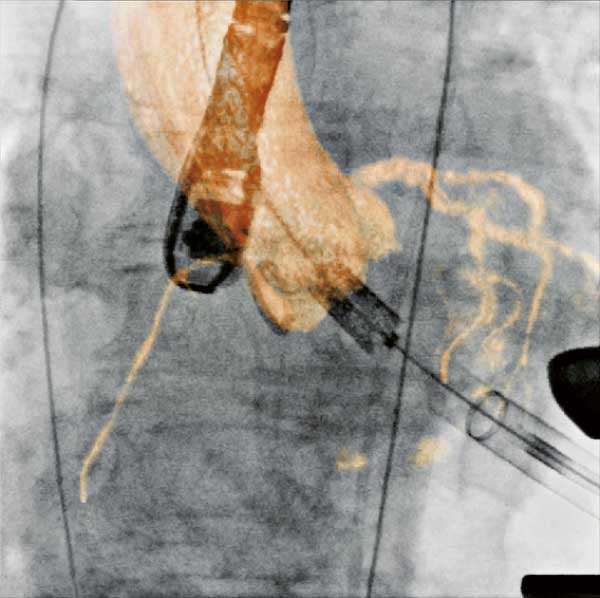

![]() |

| Figure 3. Visualization of the coronary sinus with 3D CT-like imaging. The coronary sinus can be overlayed over live fluoro and thus offers the surgeons or interventionalists the ability to navigate live in 3D anatomy (3D-Roadmap). Imaging: Courtesy of Dr. Gallagher, Central Baptist Hospital, Lexington, Kentucky, USA |

Pacemaker and ICD implantation

Pacemakers and implantable cardioverter defibrillators (ICD), particularly bi-ventricular systems, may be optimally implanted in a hybrid OR environment, because the hybrid operating theatre offers the required superior angulation and imaging capabilities in comparison to mobile C-arms and the higher hygienic standards compared to cathlabs. (Figure 3)